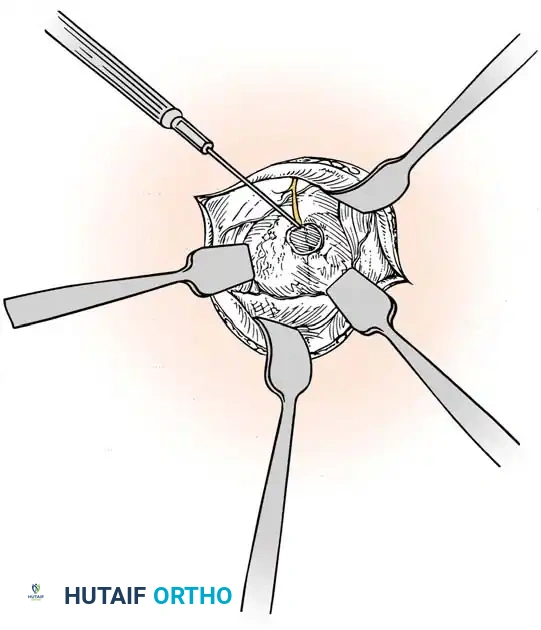

Careful separation of the ganglion from the surrounding extensor tendon sheaths.

- Stalk Excision: Using a combination of sharp and blunt dissection, mobilize the ganglion in its entirety. Trace the stalk down to its capsular origin at the dorsal scapholunate ligament. Excise the cyst along with a 1-cm margin of the dorsal capsule. Do not excise the substance of the scapholunate interosseous ligament itself, as this will cause carpal instability.

Excision of the ganglion stalk along with a generous margin of the dorsal joint capsule.

- Neurectomy: Identify the terminal sensory fibers of the posterior interosseous nerve (PIN) at the floor of the fourth compartment. Divide the nerve and gently cauterize the proximal end to denervate the dorsal capsule and reduce postoperative pain.

Cauterization of the capsular margins and the terminal branches of the posterior interosseous nerve.